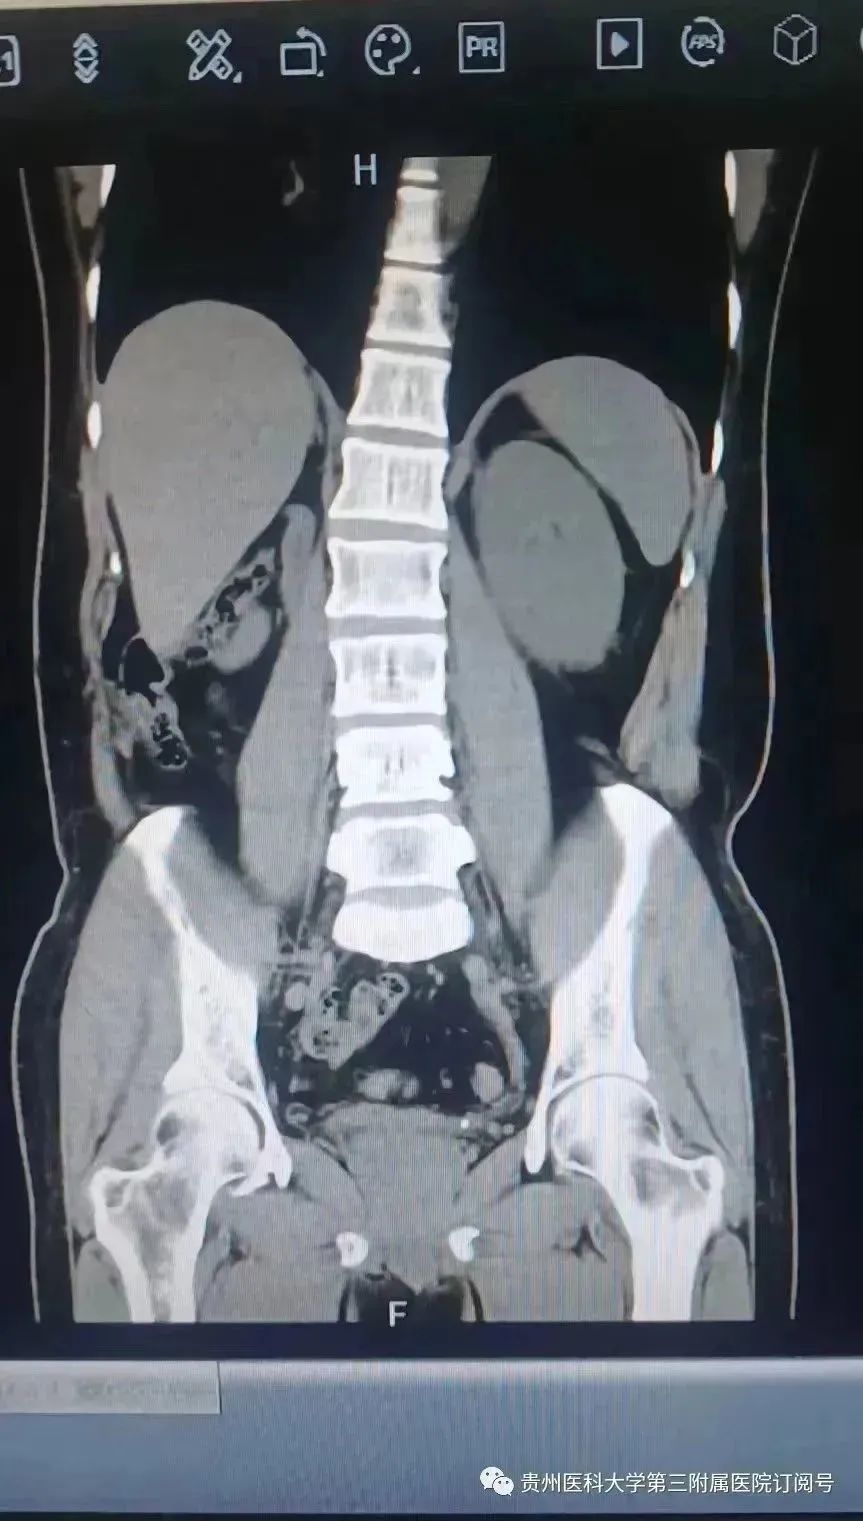

近日,在匀工作的罗先生,因“无尿20余小时”急诊于我院泌尿外科。副主任医师王帅接诊得知,罗先生2天前已出现左侧腰腹部胀痛,10多年前因肾结石已切除右肾,予以急诊CT见左侧输尿管结石导致左肾积水。

为避免肾功能急剧下降,经与罗先生及家属沟通,完善术前评估后,立即急诊行内镜手术,术中发现患者因输尿管狭窄有一颗结石堵塞,导致急性肾功能不全。手术顺利解除梗阻,成功为罗先生保留左侧肾脏的功能。